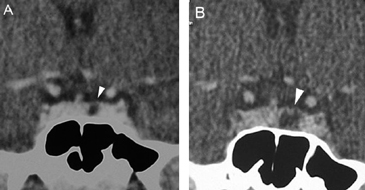

A diferencia de la tomografia computada, que emplea tubos de rayos X, la RM no utiliza radiaciones ionizantes, lo que es una ventaja a considerar en los pacientes pediátricos y en las mujeres embarazadas. La RM tiene una excelente resolución espacial y de tejidos blandos; por ejemplo permite precisar la presencia o ausencia de la neurohipófisis, lo que no es posible con la Tomografia Computada5-7. Con la TAC, con o sin medio de contraste yodado, es posible detectar microadenomas y macroadenomas pituitarios (Figuras 1A y 1B); sin embargo, en los macroadenomas puede ser difícil distinguir las relaciones del tumor con el quiasma óptico, o definir la invasión del seno cavernoso. Además, los artefactos producidos por amalgamas dentales deterioran las imágenes y la dificultad para lograr posiciones cómodas para los pacientes, con el fin de obtener cortes coronales directos, limitan la utilidad de la TAC.

Figura 1A y B. TAC con contraste yodado, corte coronal, muestra un microadenoma lateralizado a izquierda (punta de flecha). Control a los 2 años. TAC con contraste yodado, corte coronal, demuestra aumento de volumen del microadenoma, lo que es infrecuente de observar en clínica (punta de flecha).

En los microadenomas el crecimiento tumoral es observado en una minoría de los casos (Figuras 1A y 1B), en contraste con los macroadenomas, los cuales cuando son encontrados en forma accidental (incidentalomas pituitarios) han demostrado un aumento de tamaño que varía entre 25 a 50%27-31.